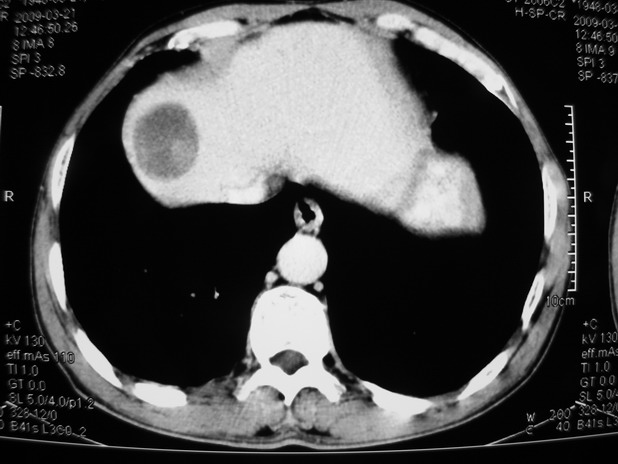

以下是引用余辉在2009-3-21 21:36:00的发言:[br]图像太乱了,建议楼主直接将强化数据按顺序列出来,病灶位置较表浅薄,有肝炎病史,灶内实性成分有显著强化,动脉期约60hu,考虑肝癌可能性大,进一步检查。